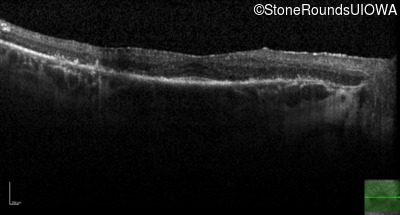

Optical Coherence Tomography - Left - 20/25 -1

Exemplar / OCT Stack